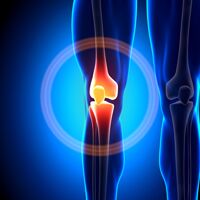

Αρθροπλαστική Γόνατος

Τι είναι η Αρθροπλαστική Γόνατος;

Η αρθροπλαστική γόνατος είναι μια χειρουργική επέμβαση που αντικαθιστά τις φθαρμένες ή κατεστραμμένες επιφάνειες της άρθρωσης του γονάτου με τεχνητά εμφυτεύματα. Η επέμβαση στοχεύει στην εξάλειψη του πόνου, στη βελτίωση της κίνησης και στην αποκατάσταση της λειτουργικότητας του γονάτου.

Αρθροπλαστική Γόνατος